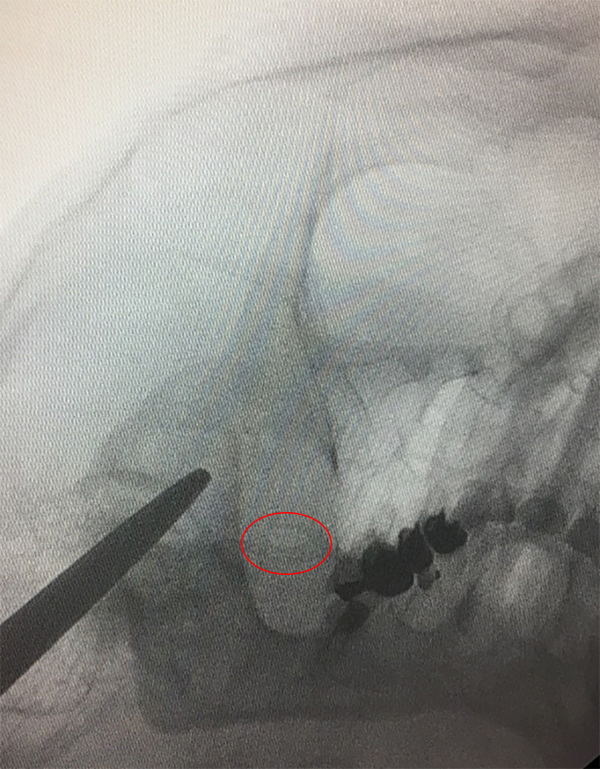

En todos los casos se colocó el paciente sobre la camilla de cirugía apoyando la cabeza sobre un cabezal radio lucido, se giró la cabeza levemente 20° aproximadamente hacia el lado opuesto a la neuralgia, allí se marcó luego los puntos de Hartel: un punto inmediatamente medial y debajo de la pupila, un punto a 3 cm delante del conducto auditivo externo para obtener la trayectoria rostral/caudal y medial/lateral respectivamente. El último punto se ubicó a 2.5 cm lateral a la comisura labial. Se realizó radioscopia para objetivar el foramen oval homolateral al dolor (fig. 1). Se procedió a realizar sedo analgesia en el paciente con propofol. Bajo radioscopia y previo campo estéril se realizó la punción, a 2.5 cm en sentido lateral a la comisura labial intentando introducir la cánula para termocoagulación por radiofrecuencia de 10 cm con punta recta de 5 mm por el foramen oval en su porción medial, una vez canulado el foramen y dentro de la cisterna trigeminal se objetivó la mayoría de las veces, no siempre, la salida de líquido céfalo raquídeo (LCR) (fig. 2). Se realizó radioscopia en sentido lateral tomando como referencia el piso de la silla turca y el clivus a 5 mm, 10 mm o 15 mm según cual rama se quiso estimular, rama V1, V2 o V3 respectivamente (fig. 3). Se conectó la aguja al electrodo de radiofrecuencia previamente conectado al dispositivo generador de radiofrecuencia (FL Fisher Neuro N50) (fig. 4), para estimular la rama motora a 5 Hz, una vez despierto el paciente se procedió a realizar estimulación a 50 Hz para objetivar el patrón de dolor habitual.

Figura 2: Introducción de la Cánula.